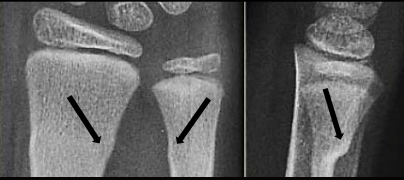

Your child has been diagnosed with a Buckle fracture. It is called a Buckle fracture because one side of the bone buckles upon itself but does not disrupt the opposite side; it is an incomplete fracture. Buckle fractures only occur in children because they have softer bones than adults.